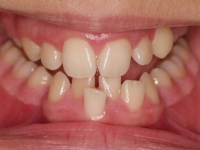

La paciente O.O. acude a nuestra consulta por:

– Canino 13 e incisivo lateral 42 en posición ectópica.

– Canino 23 incluido.

Con lo que decide realizarse un tratamiento de ortodoncia de duración de 24 meses con brackets damon Q.

CASO COMPLETO: